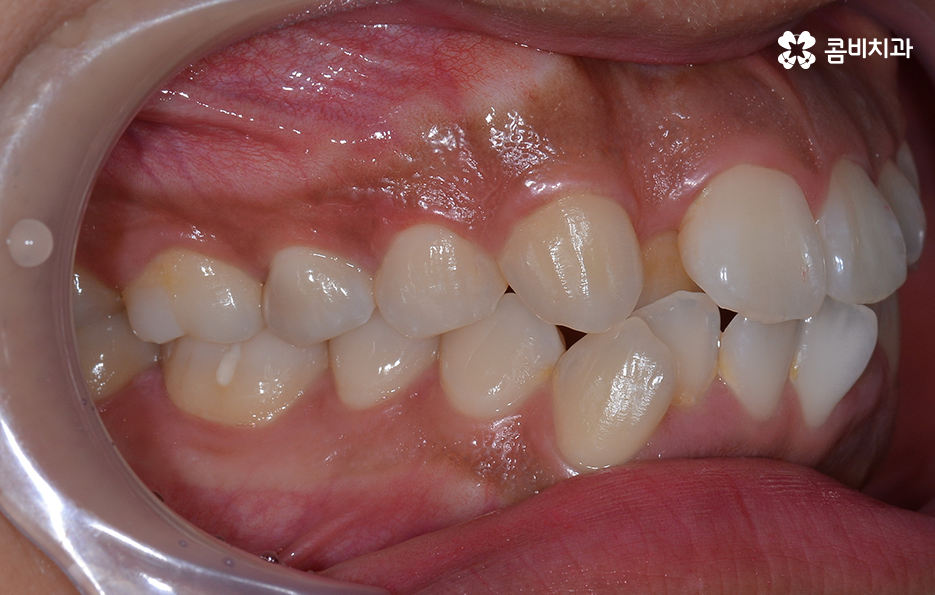

덧니의 주된 원인이 턱뼈가 좁아서 치아가 자랄 공간이 부족하다 보니 덧니의 형태로 영구치가 자라는 경우가 많다 보니 전체 치열을 가지런하게 재배열 하기 위해서는 충분한 치아의 이동 공간이 필요하고 치아의 이동 공간을 확보하는 방법으로 주로 소구치 즉 작은 어금니를 발치하는 발치교정 방식이 보편적으로 많이 활용되고 있는데요

치아를 이동시키기 위한 공간 확보 방법은 악궁확장이나 어금니를 후방으로 이동시키는 방법, 치간 삭제와 같이 비발치적인 치료 방법도 있으나 비발치적인 교정 방법으로는 한계가 있고 오히려 비발치 뻗침과 같은 부작용이 예상되는 경우에는 소구치 발치를 통한 발치 교정 방법이 적합한 경우 많기 때문에 결론부터 말씀드리자면 1:1 맞춤형 치료를 하는 것이 맞으나 덧니가 심할수록 발치교정이 적합한 경우가 좀더 많다고 볼 수 있어요

치아교정을 위한 발치교정 과정은 대부분 소구치 라고 불리는 첫번째 작은 어금니를 발치하게 되며 좌우, 위 아래 총 4개의 소구치를 발치한 후에 덧니가 재배열 될 수 있는 공간을 만들기 위하여 우선 송곳니를 후방으로 이동시키고 있어요